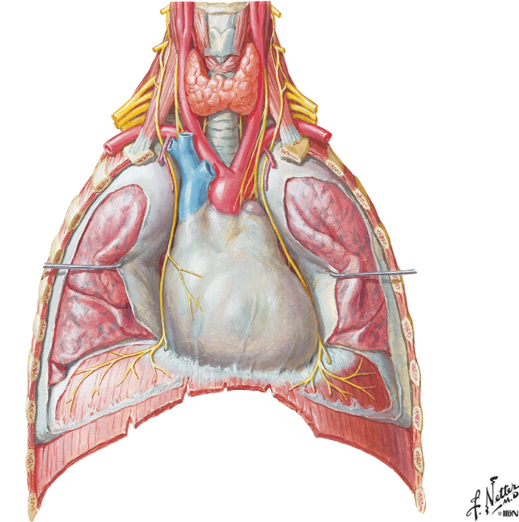

what nerve supplies the diaphragm? what 2 components does it provide? this nerve comes out of which vertebrae?

phrenic nerve (C3-C5)

motor and sensory components

the phrenic nerve passes over what as it goes down to the diaphragm?

notice the R and L phrenic nerve going down to attach to the diaphragm

the anterior scalene